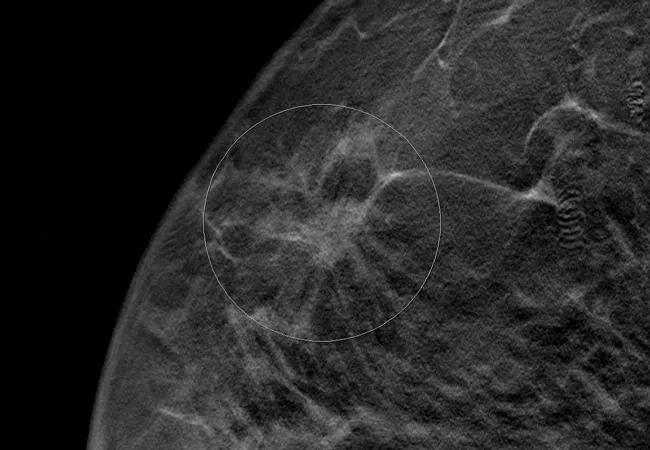

breast-cancer_650x450